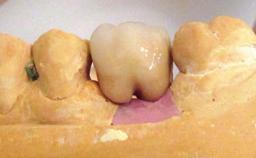

| Prosthesis Type | FDP |

| Retention | Cemented, with prosthesis margin < 3mm submucosal Cemented, with prosthesis margin < 3mm submucosal |